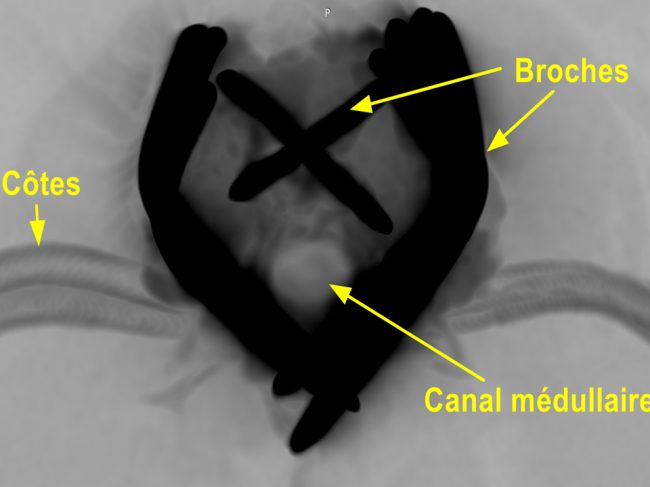

2026-01-01_174525

Stabilisation chirurgicale d’une luxation vertébrale T13–L1 post-traumatique chez un Berger australien.

De gauche à droite et de haut en bas, cette série d’images illustre la prise en charge chirurgicale d’une luxation vertébrale T13–L1 consécutive à un accident de la voie publique. La première image montre la reconstruction tridimensionnelle préopératoire, la flèche verte identifiant précisément le site de la luxation vertébrale. La seconde image correspond au début de l’intervention chirurgicale, avec exposition du foyer lésionnel et réduction progressive de la luxation à l’aide de daviers, sous contrôle visuel strict. La troisième image illustre l’implantation des broches de stabilisation vertébrale, un temps particulièrement délicat nécessitant un positionnement millimétrique selon des angles prédéfinis à partir de l’analyse scanner préopératoire. La quatrième image montre l’ensemble des broches une fois mises en place dans le rachis, assurant la stabilisation segmentaire. La cinquième image correspond à la phase de consolidation du montage, après recoupe des broches et mise en place d’un ciment de polyméthylméthacrylate permettant de solidariser l’ensemble. Enfin, la dernière image présente le contrôle scanner post-opératoire immédiat, confirmant le positionnement correct des implants, l’absence de pénétration dans le canal médullaire et la restauration satisfaisante de l’alignement vertébral.